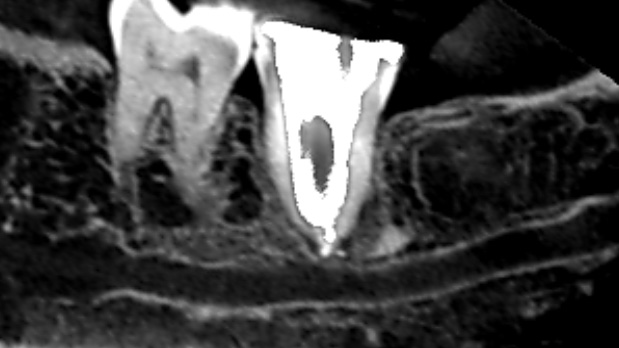

初診時のCT画像です。

この歯の歯根の水平断のCT画像です。樋状根という雨樋の様な形をしています。

樋状根は根管も雨樋の様な形をしており、隅々まで根管を清掃するのは難しく、根管に感染が残りやすいです。雨樋状(U字形)に清掃することができていないために、根管の中の感染物質が除去できず、膿んできてしまったと考えられます。